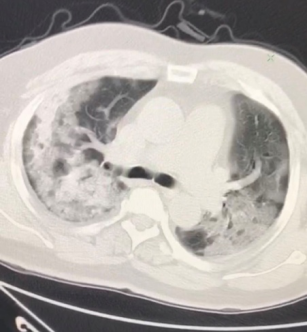

2020年1月27日中午12点,张志华、李福龙、赵建清、崔书君接到张家口市卫生健康委通知,被任命为抗击疫情的省专家组成员,要求火速去市传染病院集结,负责张家口地区感染者的救治工作。至此,张家口市抗“新冠肺炎”的战役打响了。李福龙是麻醉科及重症医学科主任,一位有着32年党龄的老党员,在党旗的指引下,参加过97年张北县大地震的救治;2003年抗击“非典”战役时被任命为队长,带领24人奋战在一线;2009年又参加了“甲流”的救治工作。此次直觉和经验告诉他“狼”又要来了。走的时候他对学医的儿子说:“你即将成为一名医生,这也将成为你的使命。”,说完便带上了早已备好的行囊出发了。1月29日,他们接诊了张家口地区最危重的,56岁合并高血压的“新冠”肺炎患者,氧合指数仅为39.3。李福龙主任每天只有1~5小时休息时间,甚至不食不眠调整医疗方案,总结治疗经验,终因过度劳累,导致胃肠功能紊乱。多年的临床经验和勤勉尽责的工作态度铸造了奇迹,第一例极危重患者10.5天脱机拔管,14天出院,并且精神状态良好的接受了电视台的采访,集体受到市委书记的表扬。他们团队趁胜追击,通过复制前者的治疗,成功的将第二位合并有糖尿病,氧合指数为60的72岁危重症患者治愈,且上机时间缩短为6.5天。引用李主任的一段日记,让我们感受一下胜利的喜悦“2.14早5点46分当看到血气时,一颗悬着的心终于落地了,平安顺利完成了落地任务。两例极危重症患者的成功救治,真的是奇迹,真的是伟大。我抬起自己的头右手掌摸着自己的前胸,一股心酸的泪水顺着脸颊刷刷的刷刷的流下来,马上走到镜子前面,打开水龙头后我用力的洗着脸,眼泪和水流在一起,有一点点哽咽,轻轻地咬着嘴唇,仰起自己的头,并左右抻了抻自己酸困几天的脖颈,左右使劲地摇摆,舒服一点了。我一边洗澡一边哭一边唱着没有水准的歌,总是在哽咽,眼皮肿肿的,眼睛红红的。我们顶住了压力,真的,我们胜利了!我们这个团队胜利了!这一刻似乎等的太久太久。静寂的房间里只有自己红红的湿润的眼睛还在模糊。天亮了。”

治疗期间,此团队根据国家卫生健康委不断更新的《新型冠状病毒肺炎诊疗方案》进行治疗,并依托厚实的理论知识和实际情况,调整了自己的诊疗方案,如:治疗窗提前、负平衡的容量管理、充分镇静镇痛肌松、俯卧位通气、肺保护性通气策略等治疗方法,收到了显著的治疗效果,做到了患者“0”死亡,医务人员“0”感染,光荣的完成了省委省政府给予的任务。省委书记王晓东赞许道:“你们经得起了大考“。李福龙主任总结:国家给的治疗方案是“道”,我们的治疗是“术”,两者需灵活有机的结合起来。师者,所以传道授业解惑也。平时的学习工作中李主任给我们授业解惑,疫情当前,他用赴死的行动为我们完成了“传道”。他是赴死的战士,人民的英雄。